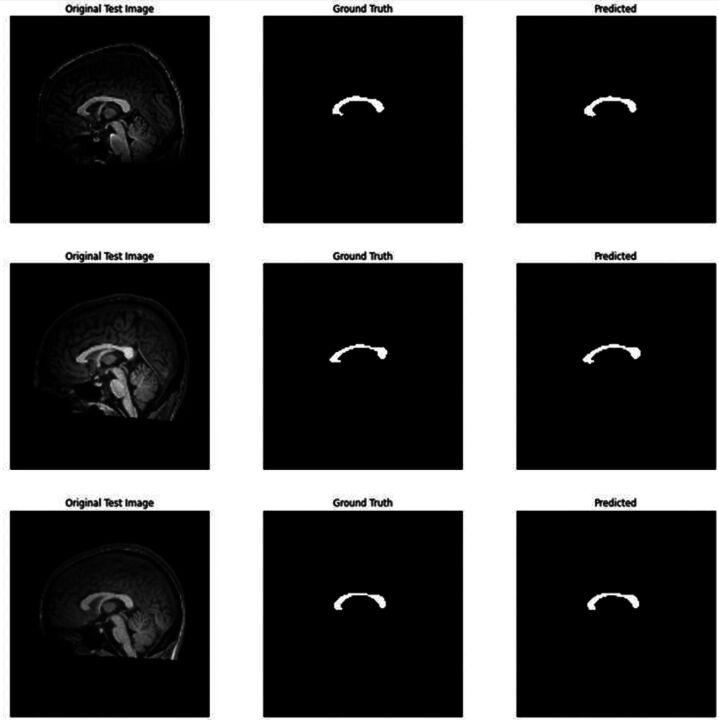

In this study, 150 MS patients (disease duration 12.6±5.9 years) and 150 healthy control subjects were scanned. Corpus callosum index was manually measured from the mid-sagittal slices on MRI. A deep learning architecture-based U-Net model was used for automatic corpus callosum segmentation from 2D brain MRI.

The CCI score was calculated as mean 0.274 in the patient group and 0.382 in the control group (=0.01). According to the ROC analysis, it was observed that the CCI measurement had a discrimination rate of 98.3% between groups with a cut-off value of 0.334. Sensitivity and specificity were calculated as 94%. The mean CCI calculated automatically after segmentation in the patient group was 0.286.

在本研究中,对150例MS患者(病程12.6±5.9年)和150例健康对照者进行了扫描。从MRI的正中矢状位切片上手动测量胼胝体指数。使用基于深度学习架构的U-Net模型从二维脑MRI中自动分割胼胝体。

患者组的CCI评分平均为0.274,对照组为0.382(=0.01)。根据ROC分析,观察到CCI测量在两组之间的判别率为98.3%,截断值为0.334。敏感性和特异性计算为94%。患者组分割后自动计算的平均CCI为0.286。